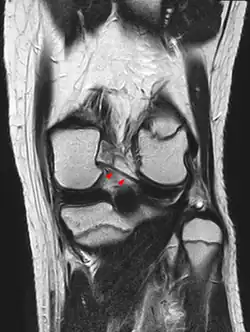

The posterior meniscofemoral ligament (also known as the ligament of Wrisberg) is a small fibrous band of the knee joint. It attaches to the posterior area of the lateral meniscus and crosses superiorly and medially behind the posterior cruciate ligament to attach to the medial condyle of the femur.[1]

The posterior meniscofemoral ligament is found in 64.4% of the subjects in MRI scan of the knee.[1]